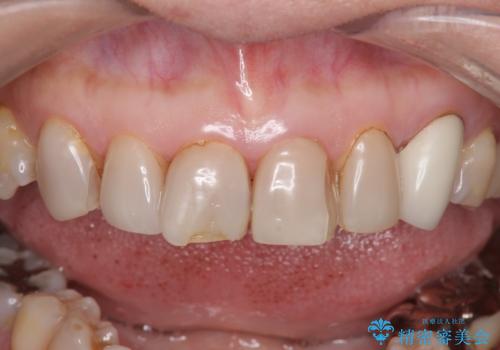

- 前歯の色や形を全体的に綺麗したいといらっしゃった方の症例です。

上顎は左側 4 番目から右側 4 番目までの 8 歯をオールセラミッククラウンで補綴しました。

今回用いたオールセラミッククラウンはジルコニアフレームという白い素材の上にセラミックを盛っているため、審美性が非常に高いのが特徴です。